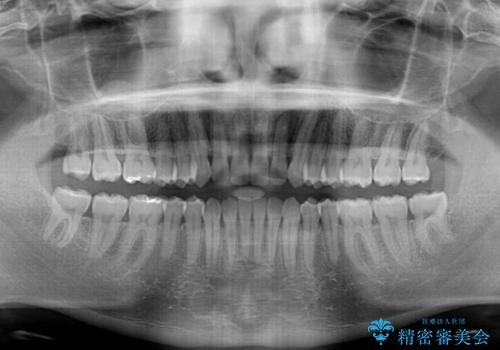

すきっ歯の改善 インビザライン矯正治療

- 上の前歯の隙間を気にして来院された患者様です。

インビザラインにより、上下の歯列を側方に拡大しつつ、前歯の隙間を閉じていくこととしました。